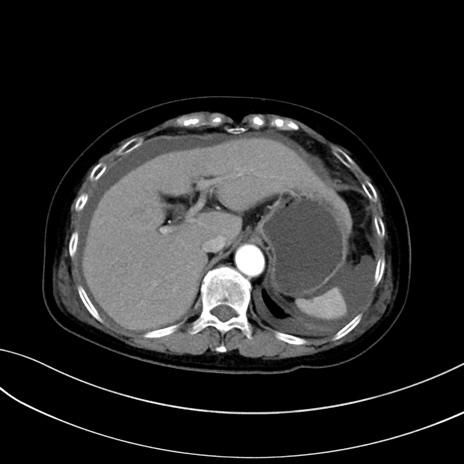

症例13 CT(横断像)1日半後